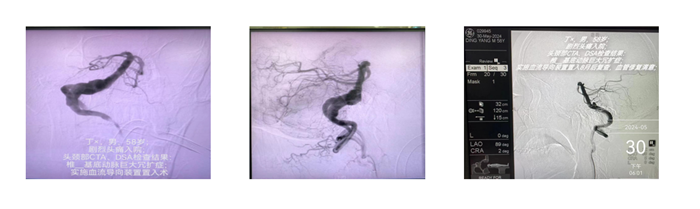

第二位患者是丁先生,8个月前的一天早晨,丁先生在晨练时突发剧烈头颈部疼痛伴言语不清,被路人发现后呼救120护送我院,经神经外二科住院总丁磊医生会诊后,安排CTA、DSA检查结果提示其椎动脉-基底动脉巨大冗长扩张症。介入治疗组任超主任团队评估病情、讨论后,决定给予丁先生实施血流导向装置置入方案,经过术后2周左右时间的治疗与康复,丁先生逐步康复出院。8个月时间过去了,目前丁先生DSA复查的结果提示其椎动脉-基底动脉术后修复良好。这样的结果使得医患双方都沉浸在这来之不易的喜悦中。

丁先生此次前来复查前后对比